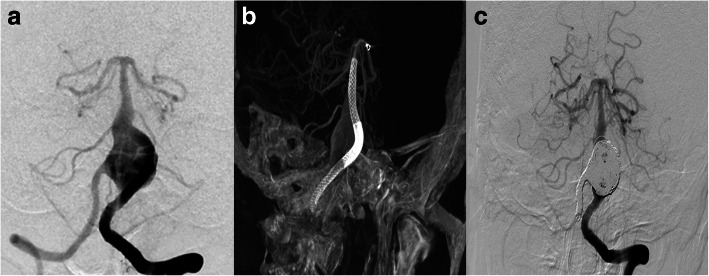

We have treated 3 patients (case 2, case 3, case 6) in total with an aneurysm whose parent artery was also the feeder of an ipsilateral AVM. Case 2 was a young female with a Spetzler-Martin grade 3 AVM of the right temporoparietal region. This diagnosis was confirmed 14 years ago when epilepsy firstly onset. This patient was on regular image follow up, and the DSA performed 10 months ago revealed a newly formed cavernous aneurysm (Fig. 2a). Since the aneurysm is the vulnerable part for rupture, we deployed a PED of 3.75 mm*30 mm to cover the neck, then loosely coiled the dome of the aneurysm with 3 coils, namely, Presidio 10 coil 7 mm*30 cm (Codman, USA), MicroPlex 10 Helical 10 mm*30 cm and 9 mm*30 cm (Stryker, USA). The total packing volume was 2.08% (Fig. 2b). 7 months angiographic follow up (Fig. 2c) demonstrated that the size of the aneurysm has decreased but still partial embolised. Case No. 3 was a 38-year-old male admitted into our department with an AVM (Spetzler-Martin grade 3) and an ophthalmic aneurysm which ruptured 45 days ago (Fig. 3a). The aneurysm measured 5 mm in length and 6 mm in width and there existed a daughter sac which presumed to be the rupture point. We then placed one PED (4.75 mm*18 mm) and further occluded it with 8 coils (Fig. 3b, c). The packing volume reached 40%. The whole procedure completed without any technical difficulties and the patient discharged without any neurological deficits, however, the patient died 20 days thereafter due to brain hemorrhage in local hospital.

Fig. 2.

Case NO. 2 was a young female with a large cavernous aneurysm and a coexisting Spetzler-Martin grade 3 AVM of the right temporoparietal region (a). Immediate postoperative angiogram (b) and 7 months angiographic follow up (c) indicated that the size of the aneurysm has decreased but still partial embolised

Fig. 3.

Case NO. 3 was an ophthalmic aneurysm with an AVM (Spetzler-Martin 3) (a), we placed one PED (4.75 mm*18 mm) and further occluded it with 8 coils (b, c)